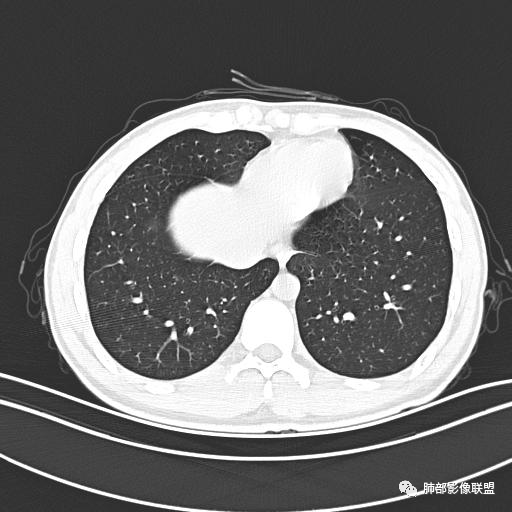

男,19岁

主  诉:发热、全身皮疹2天。

现病史:患者源于2天前受凉后出现发热,最高体温为38.5℃,且颜面部出现少量皮疹,无鼻塞、流涕、咳嗽、咳痰,未在意而未作特殊处理,次日全身皮疹逐渐增多至全身,伴轻度瘙痒,在当地卫生所给予抗病毒、抗感染治疗(具体用药不详)体温有所下降,但皮疹无明显消退,无腹痛、头痛,食欲无明显减退,为进一步诊治,遂于今日急来我院求治,患者目前精神尚可,体力正常,食欲正常,睡眠正常,体重无明显变化,大便正常,排尿正常。

小强:青年,发热,皮疹;双肺散在结节,周围磨玻璃,点晕征,疱疹病毒感染,鉴别荚膜组织胞浆菌,结核。 大雄:青年,急性起病,发热伴全身皮疹2天,抗病毒治疗体温有下降。双肺随机分布大小不等类圆结节,“点晕征”。考虑水痘-疱疹病毒(VZV)血播询问接触史,查体皮疹分布以及形态基本可诊断。 王开金江津中心医院呼吸科:青年男性,起病急,病程短,以发热,皮疹为首发症状,感染指标以单核细胞升高为主,胸部ct双肺多发结界,周围有晕,点晕表现,随机分布,同意於老师意见,水痘疱疹病毒血流感染累及肺。 王秀仙:双肺多发大小不等结节,周围有晕,边缘模糊,呈点晕征表现。青年,急性起病,发热伴全身皮疹2天,抗病毒治疗体温有下降。考虑疱疹病毒。鉴别荚膜组织胞浆菌。 傅昌瑜:19岁男性,发热、全身皮疹2天,单核细胞增高,双肺多发结节,结节边缘见边界不清磨玻璃影。点晕征+发热、全身皮疹+单核细胞增高——考虑水痘-带状疱疹病毒肺炎。 一切∮随缘:年轻男性,发热,皮疹两天,实验室,CRP,PCT增高,影像:双肺多发散在磨玻璃结节,边界欠清,大小不等,呈点晕征改变,以血管束周围分布为主,局部血管束略增粗,其它无明显改变,考虑:1:病毒性肺炎(水痘疱疹病毒?不知道皮肤有无改变)2:真菌(组织胞浆菌,血管侵袭性肺曲霉)3:GPA4:寄生虫(实验室没有看到嗜酸细胞增高) 赵山河:双肺散在结节,周围有晕,边缘模糊,呈点晕征表现。青年,急性起病,发热伴全身皮疹2天,抗病毒治疗体温有下降。考虑水痘—疱疹病毒感染。洪桥爱:青年男性,发热、皮疹2天,伴瘙痒,皮疹于面部首发,之后进展至全身,虽然没有对皮疹进行描述,但是从出疹时间及皮疹进展情况,伴瘙痒,应该就是个水痘患者;CT提示双肺随机分布结节影,部分结节伴有边界不清晕征,考虑水痘血播肺。 刘强:年轻男性,急性起病,皮疹,发热,抗感染治疗体温下降,说明有效。影像表现为散在点晕征,感染类疾病谱(疱疹病毒,真菌,结核),结合年龄,皮肤皮疹,考虑水痘-疱疹病毒性肺炎。 小兜:男性,19岁,发热皮疹两天,颜面部至全身,CRP,降钙素及单核增高。CT示双肺散在小结节,周围伴磨玻璃影,点晕征,考虑为水痘-带状疱疹病毒(varicella-zoster virus,VZV)肺炎 必有路:青年,皮疹+发热+“点晕征”→水痘-疱疹病毒(VZV) 许慧良:青年男性患者,发热、皮疹2天,体温最高38.5℃,第3天皮疹扩展至全身,伴瘙痒,胸部CT:双肺多发随机分布的小结节,结节周边见边界模糊的晕征,考虑水痘病毒感染流心明智:男,19,急性起病,发热伴全身皮疹2天。出疹顺序头→全身,抗病毒有效。胸部CT:两肺多发大小不等类圆形实性小结节影,随机分布,结节周围环绕GGO,边界模糊,呈点晕征。出疹特点是关键,未提示。考虑:血播病毒性肺炎,水痘-疱疹病毒?麻疹?鉴别荚膜组织胞浆菌、TB、血管炎、寄生虫等。 浪迹天涯:病灶多为5-10mm大小结节,结节周围可见磨玻璃样的晕环,常多发,可分布于肺内任何区域,考虑水痘—带状疱疹病肺炎如果短时间内有新的一个区域浸润,更加能说明,